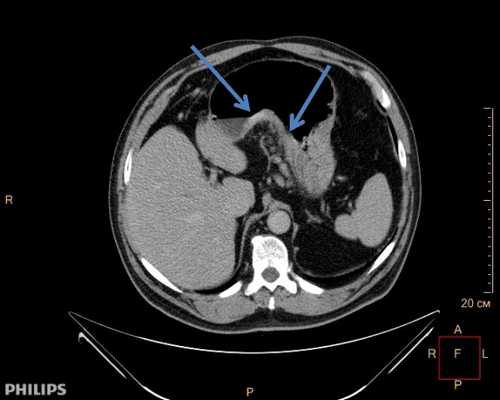

С целью выяснения степени распространенности опухолевого роста в средостении, оценки местного распространения опухоли по лимфатическим сосудам, а также для обнаружения возможных отдалённых метастазов возможно применение компьютерной томографии (КТ). Бронхоскопию выполняют для оценки возможности прорастания опухоли в трахеобронхиальное дерево. В диагностически сложных случаях возможно применение медиастиноскопии.

![КТ грудной клетки. Выраженное циркулярное мягкотканное утолщение стенки пищевода в нижней трети]()